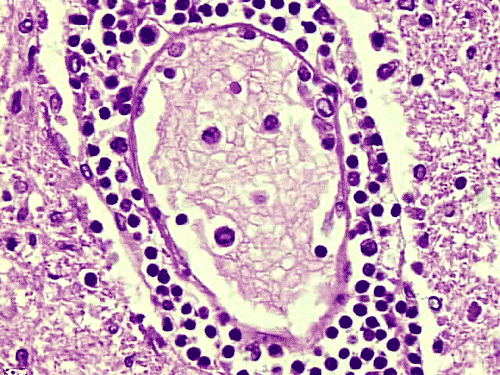

The overall tissue preservation is less than optimal because of postmortem autolysis. Panel A and B are taken from the cerebellum. The molecular layer, Purkinje cell layer, and internal granular layer are included (Panel A). Solitary eosinophilic intracytoplasmic inclusions of variable size are present in the Purkinje cells. No inflammatory cell infiltration is present in the cerebellum. The vacuolar spaces (Panel B) is partly due to autolysis and partly due to hypoxic/ischemic changes. Pyramidal cells in the hippocampus (Panel C), cortical neurons in parietal lobe (Panel D) and other neocortical areas adopted an elongated and contracted contour with loss of nuclear details. These are histologic features consistent with hypoxic/ischemic changes. Similar to the cerebellum, solitary eosinophilic cytoplasmic inclusion bodies are present and there is no inflammatory cell infiltration. Multiple eosinophilic cytoplasmic inclusion bodies within a single neuron are occasionally found. Some of these neurons containing multiple inclusions from the substantia nigra are illustrated in Panel E. Although inflammatory cell infiltration is scant in the cerebrum and cerebellum, perivascular chronic inflammatory cell infiltrations are common in the medulla (Panel F and G), in the paravertebral sympathetic ganglion (Panel H and I) and in the spinal cord (not shown). Intracytoplasmic inclusions, however, are not found in the medulla, spinal cord, and paravertebral sympathetic ganglion. Under the electron microscope, rod-shape or bullet-shaped viral particles are found (Panel J).

Rabies is an enveloped single strand RNA virus of the genus Lyssavirus in the family Rhabdovirus. This family of viruses infect a wide variety of mammals, fish, birds, and plants. The virus is rod shaped (Greek Rhabdos, meaning “rod”) and its envelope contains a G protein, an externally protruding spike of transmembrane virual glycoprotein that allows the virus to bind to cell-surface receptors to initiate fusion of the envelope with the cytoplasmic membrane and subsequent endocytosis of the virus. Receptors include the nicotinic acetylcholine receptor and neural cell adhesion molecule (NCAM; CD56) 7, 8. There is sequence homology between the G protein of rabies virus and the region with the greatest binding affinity for the acetylcholine receptor 9. The genome is a negative-sense 12-kb RNA. A positive intermediate genome is synthesized and acts as a template for the synthesis of new genomes. Replication occurs in a circumscribed region that corresponds to the Negri body (vide infra). The viral envelope is acquired by budding through the modified cytoplasmic membrane or endoplasmic reticulum of the host cell. Rabies virus is inactivated by detergents rapidly, a feature that makes local wound care and cleaning with high concentration of soap and water a critical, probably most important and efficient step in the prevention of rabies. The virus is also rapidly inactivated by exposure to ultraviolet light, sunlight, desiccation, formalin, phenol, b-propiolactone, and ether 3.

The brain and spinal cord may appear swollen but are usually free of focal lesions. Histopathologically, rabies is a widespread polioencephalomyelitis. Leptomeningeal and parenchymal perivascular lymphocytic infiltrations are usually present but often not intense. Neuronophagia can also be seen. The amount of inflammation of the case under discussion is, in fact, on the intense side of the scale. The pathognomonic Negri bodies 10, 11, 12 are sharply delineated, round to oval, eosinophilic, neuronal cytoplasmic inclusions; first described by Negri in 1903 10. These inclusions are often solitary but may also be multiple in a single neuron. Lyssa bodies refer to less well delineated and more pleomorphic neuronal cytoplasmic viral inclusions. Babes’ nodules refer to clusters of microglia that remain after destruction of neurons. When immunohistochemistry is employed, the distributions of viral antigen are far more extensive than that estimated by conventional light microscopy 13. Negri body and rabies viral antigen as demonstrated by immunohistochemistry are most commonly seen in large neurons of the hippocampus (Pyramidal cells), cerebellum (Purkinje cells), thalamus, basal ganglia, cerebral cortex and in the brain stem, especially gray matter of the pons and medulla. They are also found in spinal cord motor neurons and dorsal root ganglion, especially in the paralytic form.  Immunohistochemistry also demonstrated rabies viral antigen in astrocytes and oligodendrocytes 13. Characteristically, a striking discrepancy between the degree of inflammation and amount of inclusion bodies is observed, as in our case, in many cases.